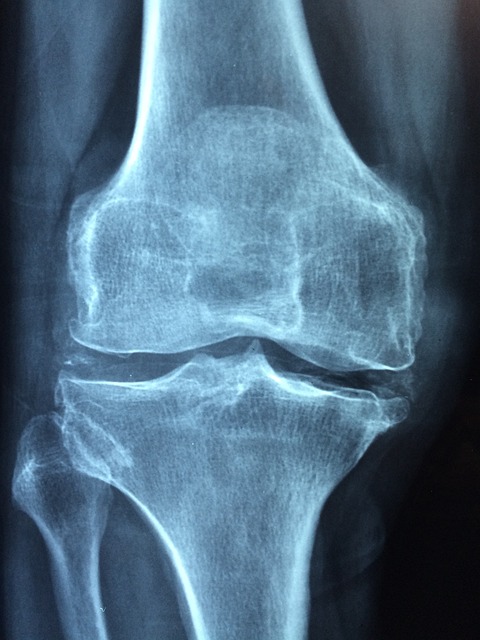

물찬 무릎의 정체

무릎 관절에는 원래 소량의 활액이 윤활유처럼 작용합니다.

건강한 무릎의 활액은 약 3ml 정도인데, 염증이 생기면 50ml 이상까지 증가합니다.

이렇게 늘어난 관절액이 무릎을 팽팽하게 만들고 움직임을 제한합니다.